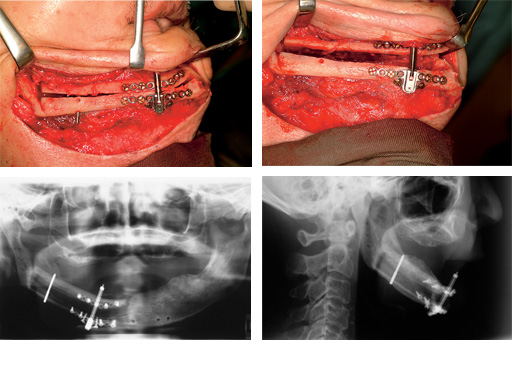

Distraction of a fibula flap in the mandibular body after tumor resection. The additional pin provides stabilization.